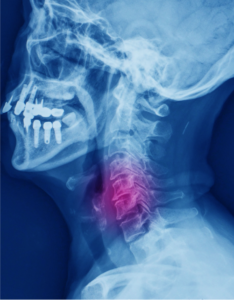

Neck Pain

The first 7 vertebral bones on the spinal column form the cervical spine and are located in the neck region. The neck bears the weight of the head…

Cervical Fracture

The neck is made up of seven tiny bones called cervical vertebrae (C1-C7). These are protected by spongy vertebral disks present between them and supported…